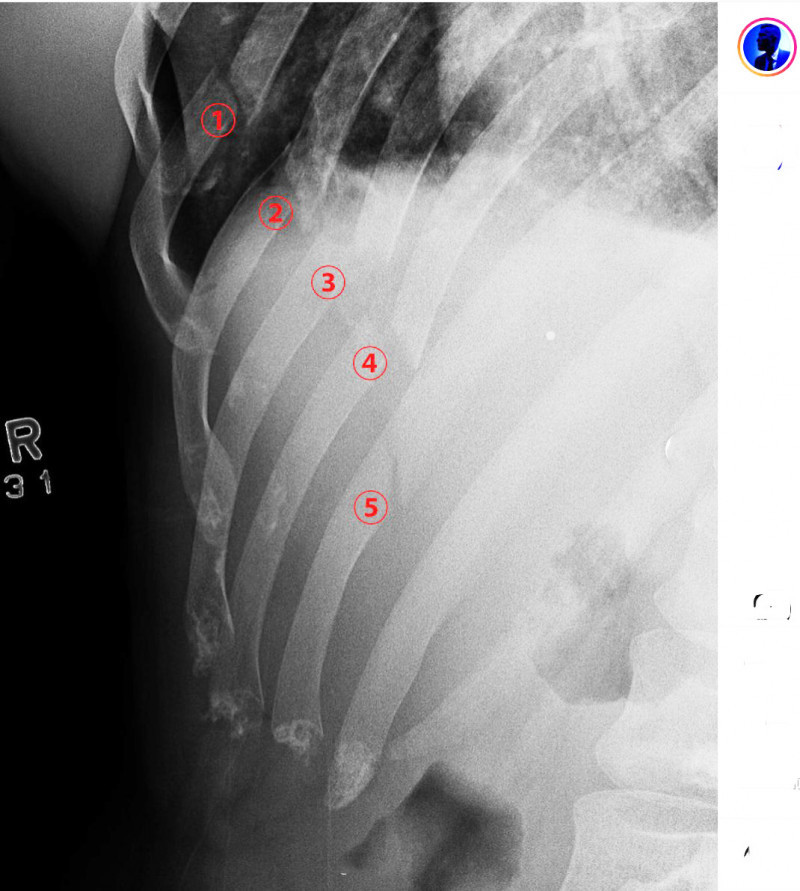

拡大レントゲン写真、肋骨5箇所が折れている@blackeagle_170より